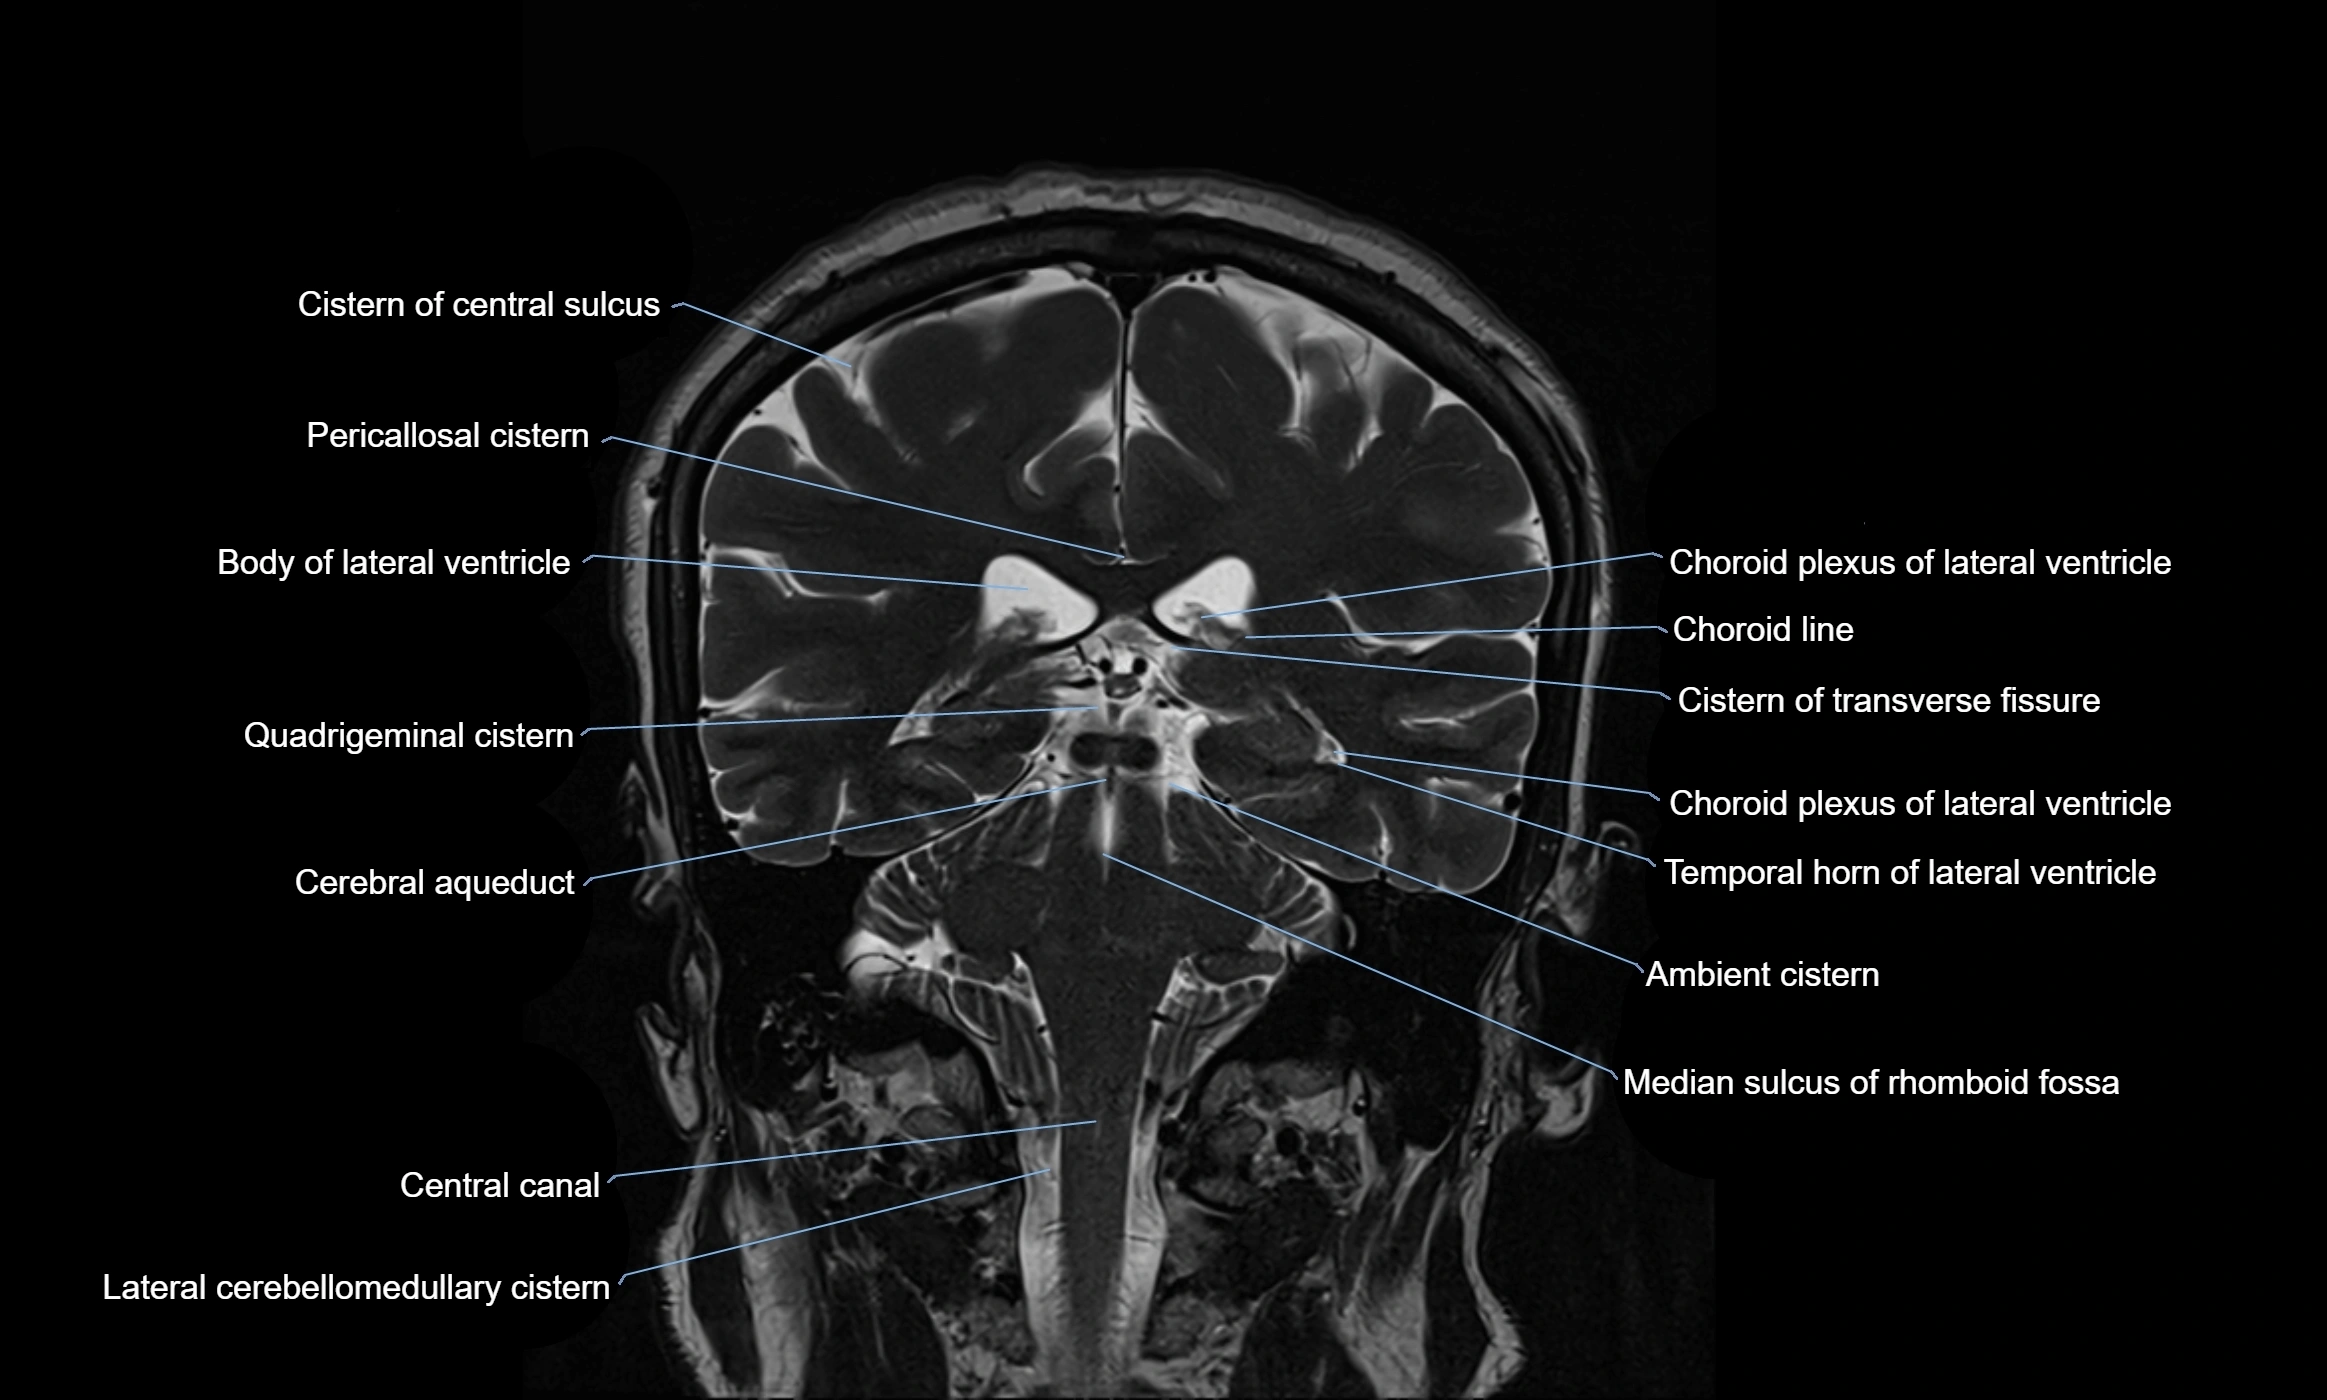

MRI images

image